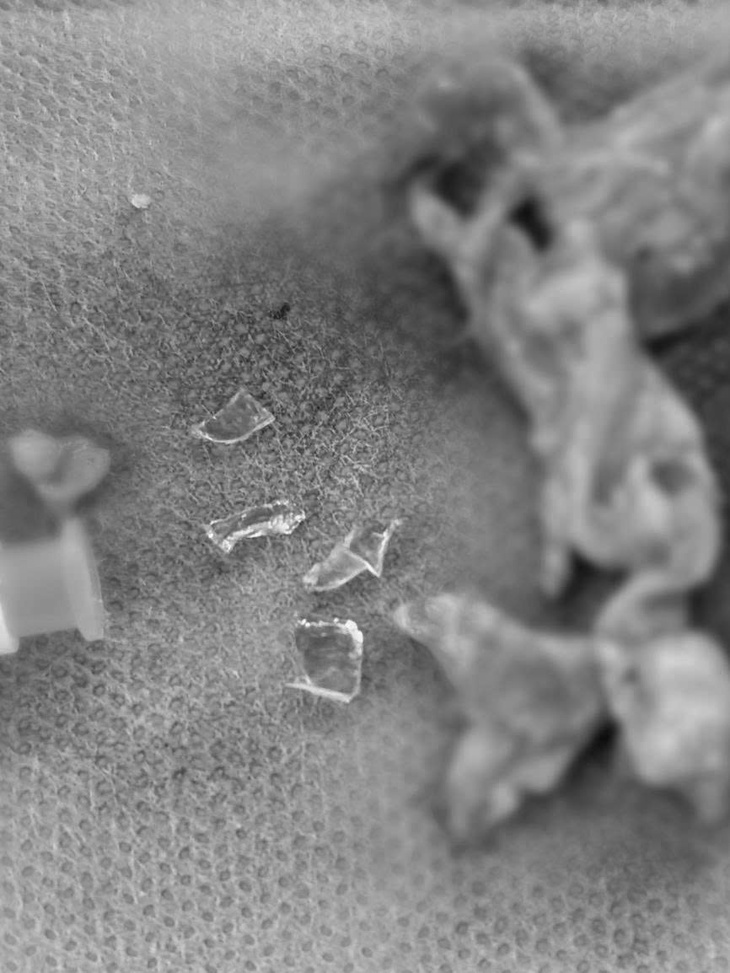

Ê-kip ghi nhận nhiều mảnh kính thủy tinh kích thước to nhỏ đâm vào sâu dưới da và xương sọ, len lỏi sát dây thần kinh cảm giác vùng trán và mắt.

’Ma trận’ mảnh kính thủy tinh kích thước to nhỏ đâm sâu vào dưới da và xương sọ - Ảnh: BVCC